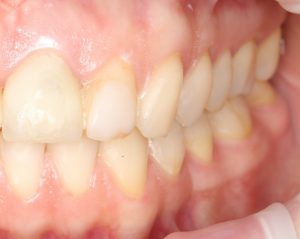

На фотографии выше, коронки опираются на обычные импланты, но даже в этом случае увеличение высоты супраструктуры усложняет гигиену и требует более пристального дальнейшего наблюдения. С ультракороткими имплантами, если честно, всё еще хуже.

Как будет выглядеть такая конструкция? Какой длины будут коронки? Возможно, на эстетику даже можно забить, ведь для некоторых людей красота зубов в боковом сегменте челюсти за пределами эстетически значимой зоны не так важна, но… как быть с уходом за протетической конструкцией и ежедневной гигиеной? Ведь, чем больше по размеру протез, тем сложнее за ним ухаживать. Тем больше мест, где может остаться зубной налет, а это, как вы понимаете, может привести к очень неприятным последствиям — периимплантиту, что для ультракоротких имплантов очень критично. А застревание пищи между протезом и десной? Можно ли назвать это «повышением качества жизни пациента»? Вряд ли.